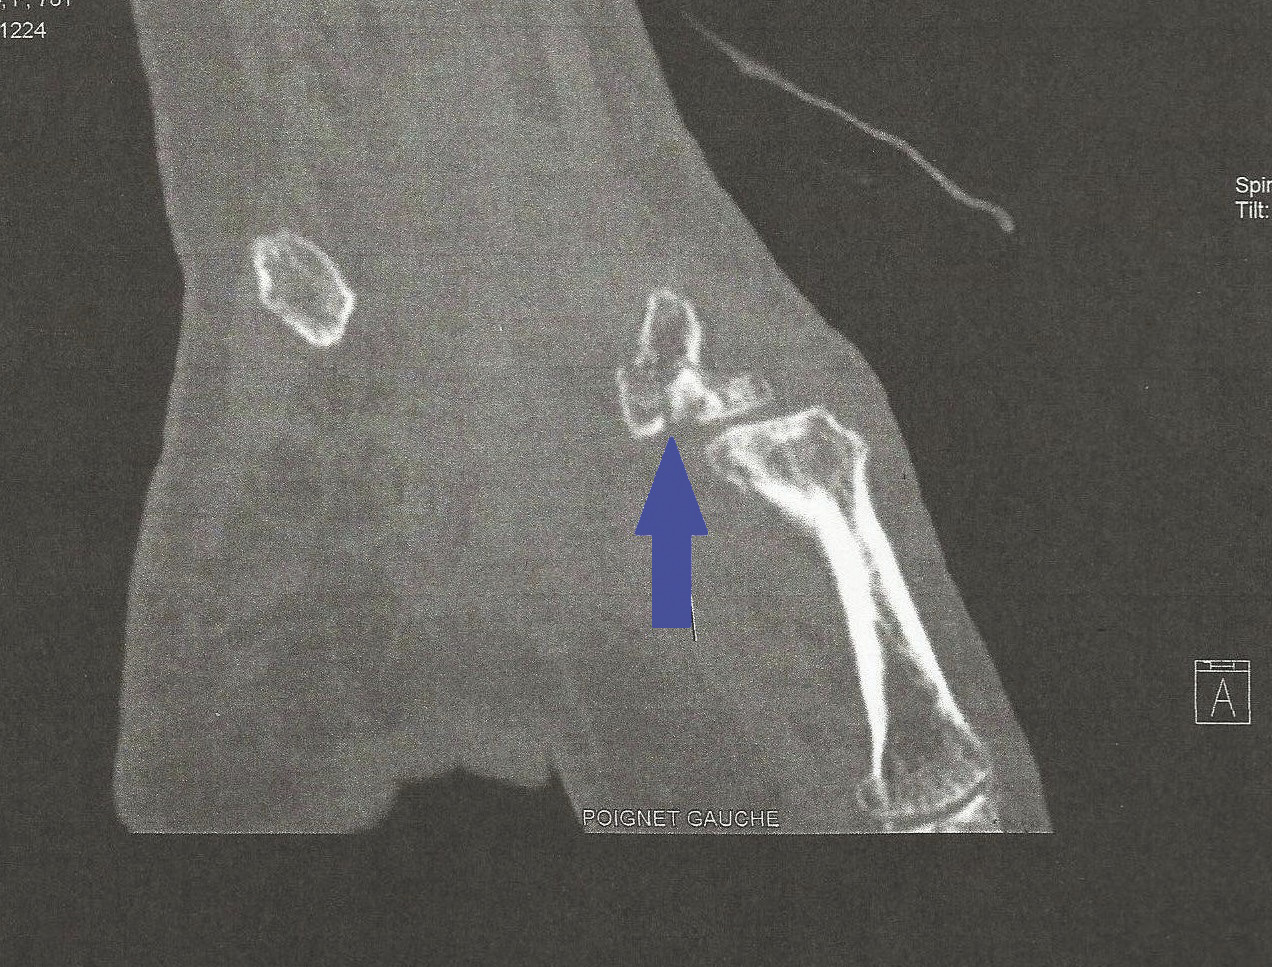

Un scanner est demandé, compte tenu de la symptomatologie persistante (figure).

De fait, le scanner du poignet est une technique plus sensible que la radiographie, permettant d’objectiver une fracture même peu déplacée du versant palmaire du trapèze (figure, flèche).